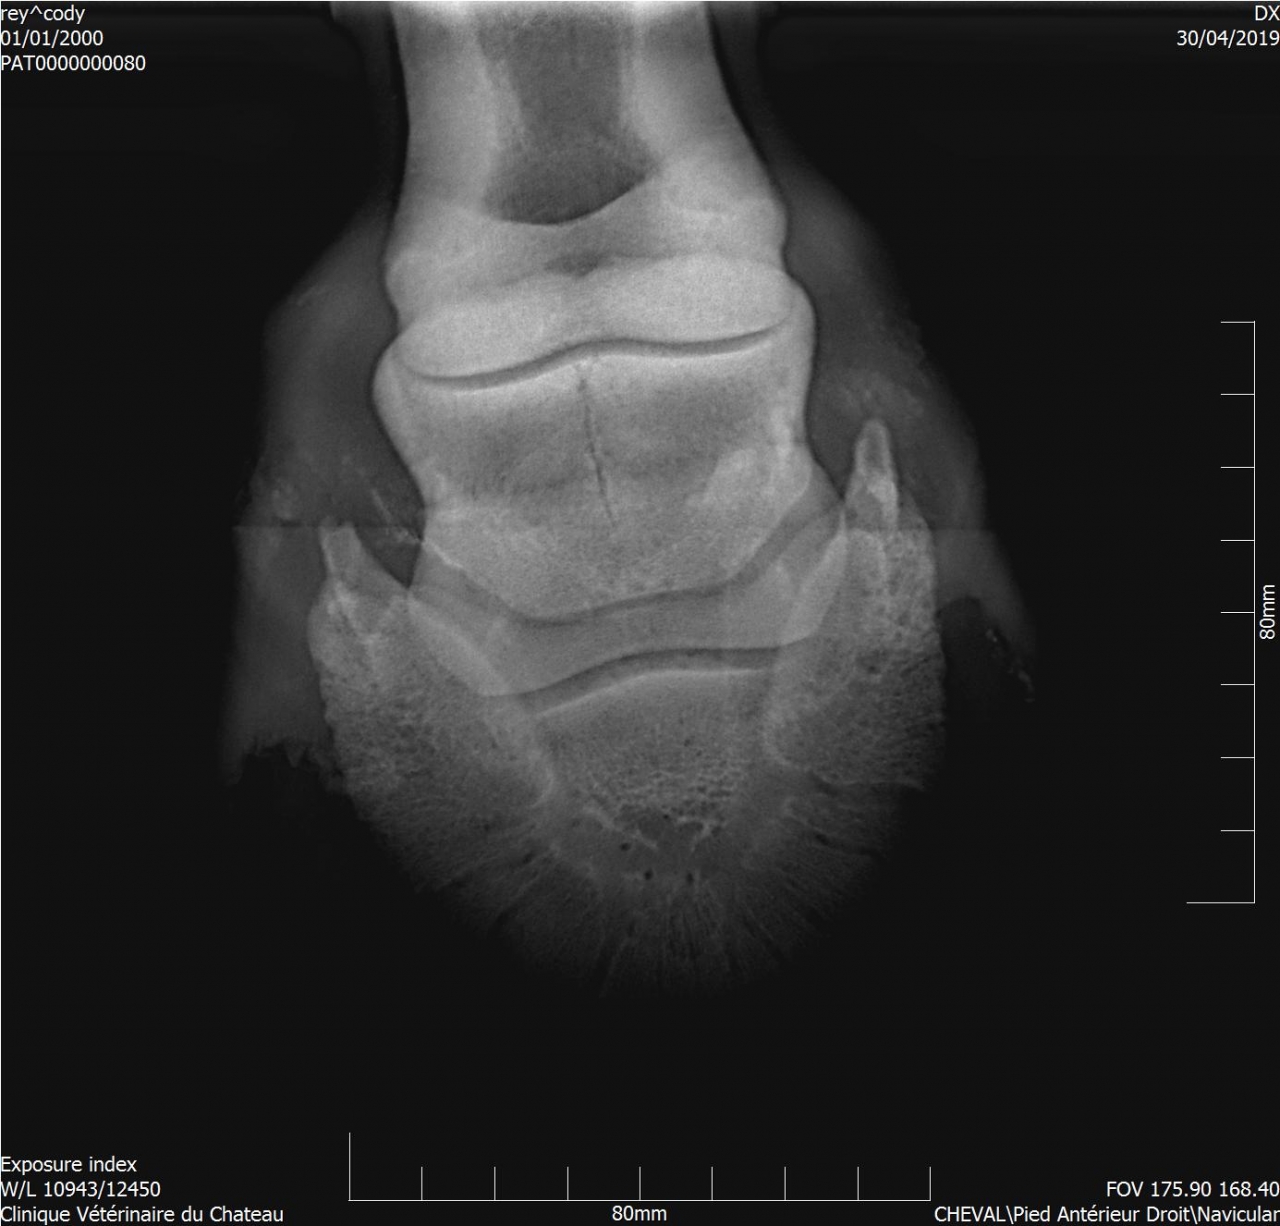

| Dire merci | Pour donner un ordre d'idée : radio de Cody.![]() |

| Dire merci | Disons que ça dépend ce qu'il voulait voir, s'il voulait les articulations c'est bon, s'il voulait une photo du pied c'est coupé c'est clair ! Mais je pense qu'il cherchait une photo des articulation, sur une photo de pied l'articulation du boulet est souvent coupée (cf radio de cody) Elle est bizarre d'ailleurs ta radio goss, on voit pas du tout la boîte cornée |

| Dire merci | La radio a été prise pour voir le naviculaire. J'en ai d'autres ![]() ![]() ![]() |